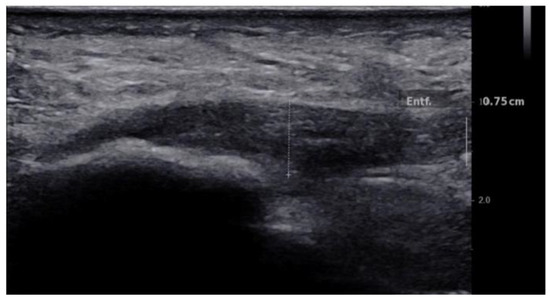

2.4.1. B-Mode US Examination